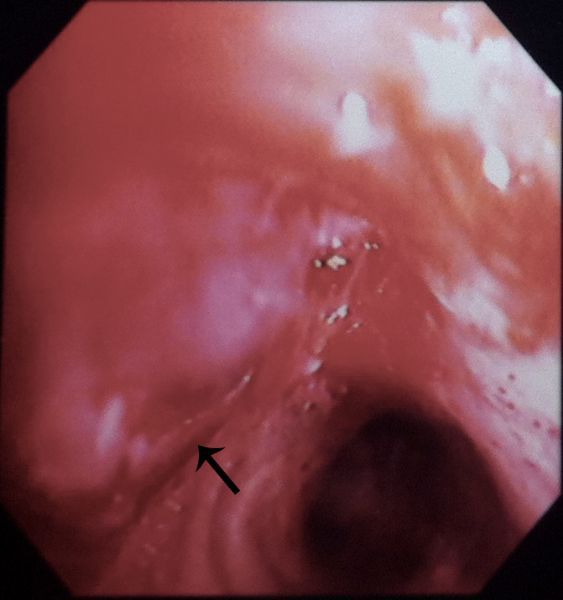

Nesta imagem obtida por broncoscopia de outro caso semelhante, observa-se oclusão do brônquio do lobo superior por lesão de aspecto liso e violáceo (seta). O anatomopatológico mostrou processo inflamatório crônico granulomatoso com necrose caseosa e pesquisa de BAAR positiva no material.

In this image obtained by bronchoscopy from another patient, there is occlusion of the upper lobe bronchus, which is filled by a smooth and violaceous lesion (arrow). Histopathological examination revealed chronic granulomatous inflammation with caseous necrosis and AFB smear positive.